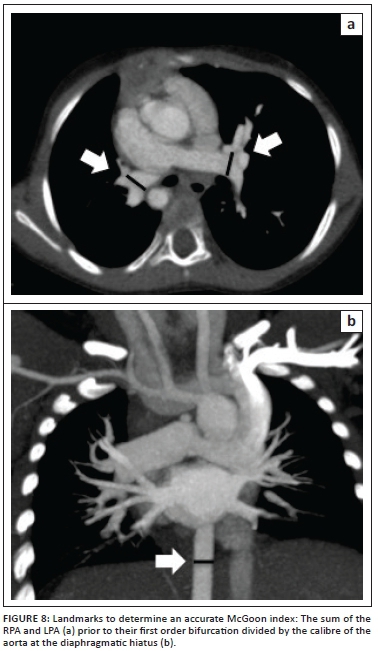

Cardiac CTA, with its multi-planar and three-dimensional reconstruction capabilities, allows accurate depiction of pulmonary artery anatomy, MAPCAs and the aorta at the level of the diaphragm. These features allow calculation of the McGoon index and the Nakata index (Figure 7) to quantitate the degree of pulmonary artery hypoplasia. The McGoon index is the preferred index in our institution and is used post-palliation (central shunt, classic or modified Blalock-Taussig shunt, Brock procedure or stent) to guide definitive repair and VSD closure when it exceeds 1.6-1.8.